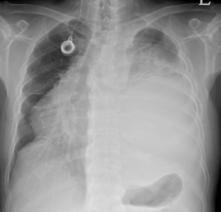

폐암 치료방법

초기라면 수술로도 충분히 치료가 가능하지만 말기이거나 전이가 된 상태라면 항암치료를 받게 됩니다. 최근에는 표적항암제라는 새로운 치료제도 개발되어 생존기간 연장 및 삶의 질 향상에 도움을 주고 있지만 부작용 우려가 있고 내성이 생길 수도 있어서 신중하게 선택해야 한다고 해요.